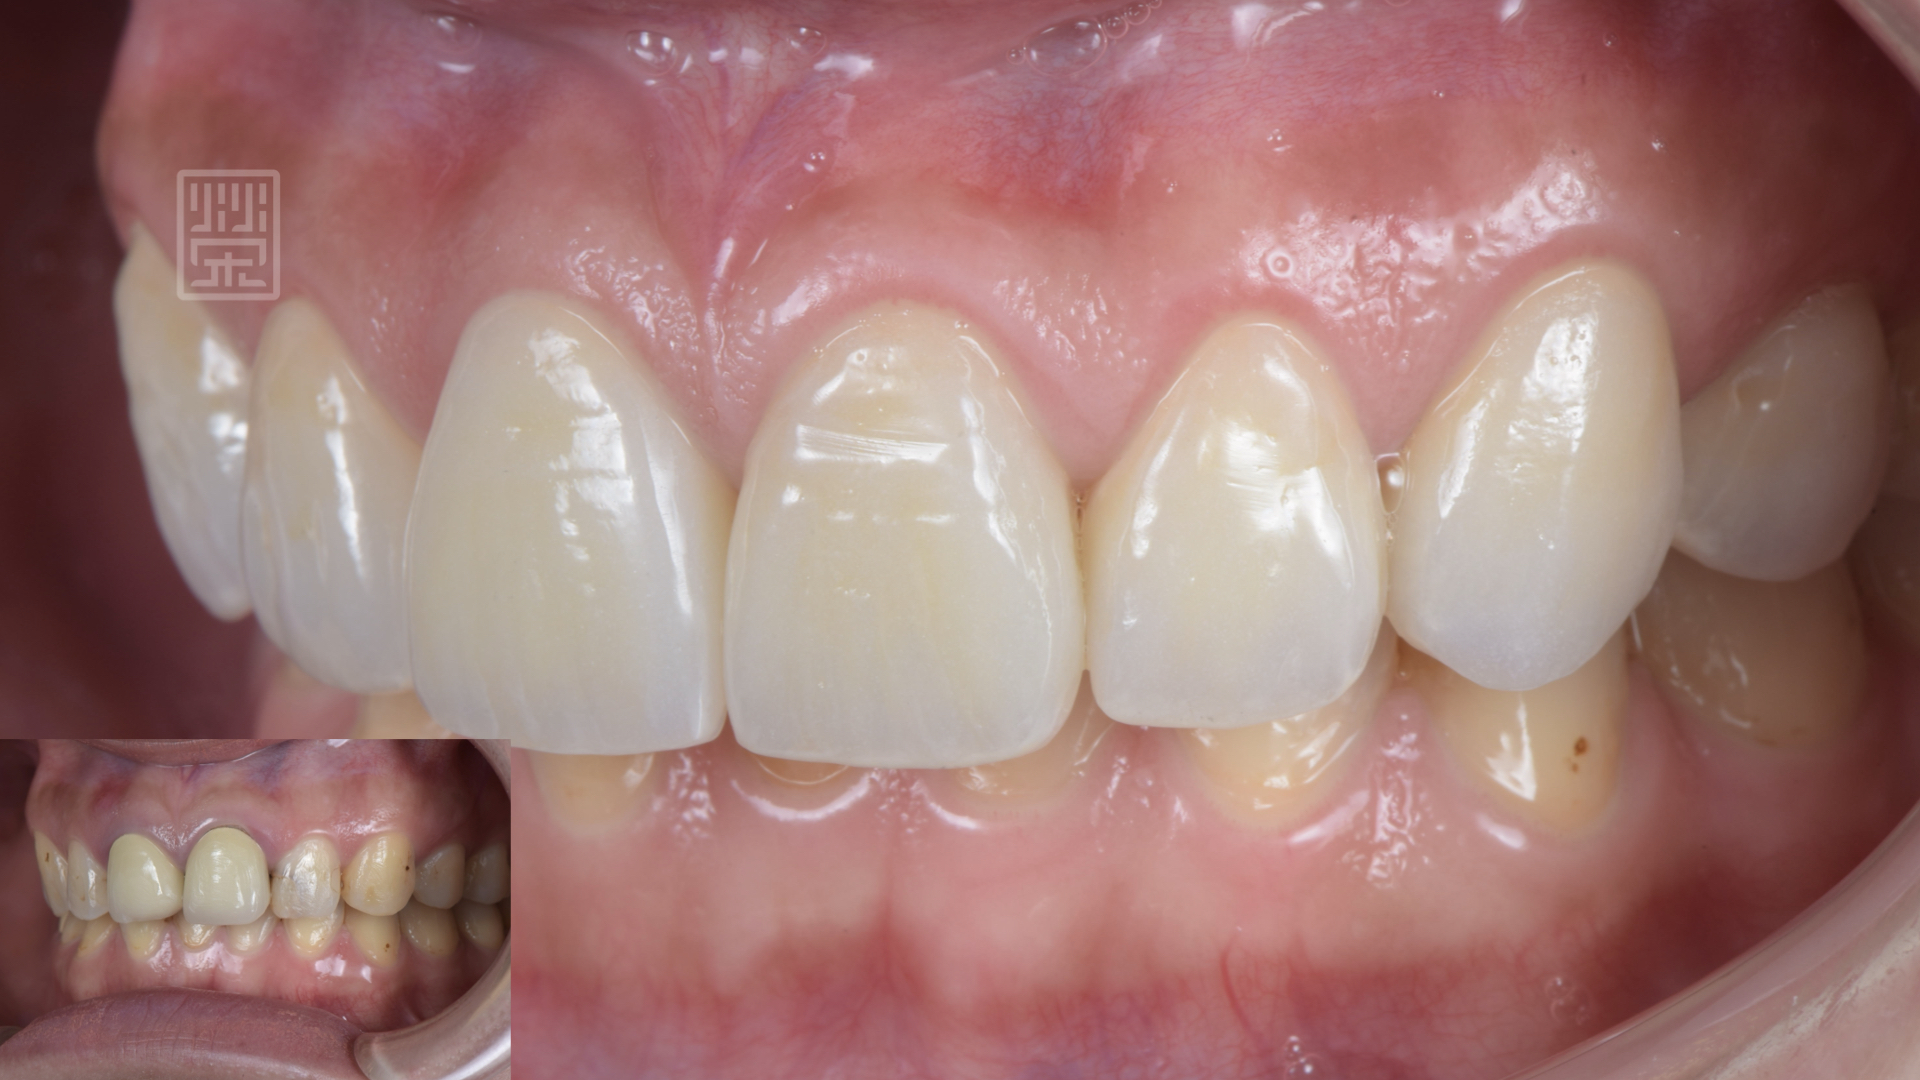

等到植體癒合穩定後,針對牙齒的長度為製作模擬溝通,顏色部分希望自然白亮即可,所以選擇自然齒色中最白亮的色階,讓整體笑容更加和諧。

植牙、全瓷冠、全瓷貼片完成

貼片全瓷冠與笑容和諧